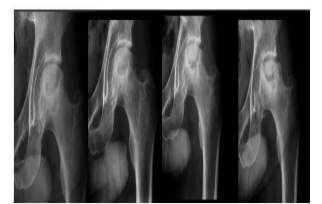

A radiologia veterinária se desenvolve a passos largos e suas aplicações têm se tornado cada vez mais presentes

no dia a dia do médico veterinário. Avalie o seguinte caso clínico: Cão da raça Yorkshire, 10 meses de idade,

apresentando claudicação grau 2 no membro pélvico esquerdo e dor à palpação coxofemoral esquerda. Os

exames radiográficos seriados evidenciaram as alterações ósseas reveladas nas imagens abaixo.

Com base nesses dados, qual o provável diagnóstico?